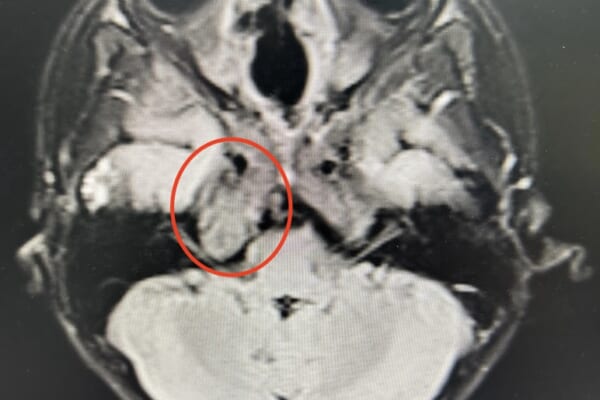

この腫瘍は聴神経から発生する良性の腫瘍(神経鞘腫)で、小脳橋角部という部分に発生するものです。聴神経には聴覚に関係する神経(蝸牛神経)と平衡感覚に関する神経(前庭神経)があり、前庭神経から発生するものが多いとされています。